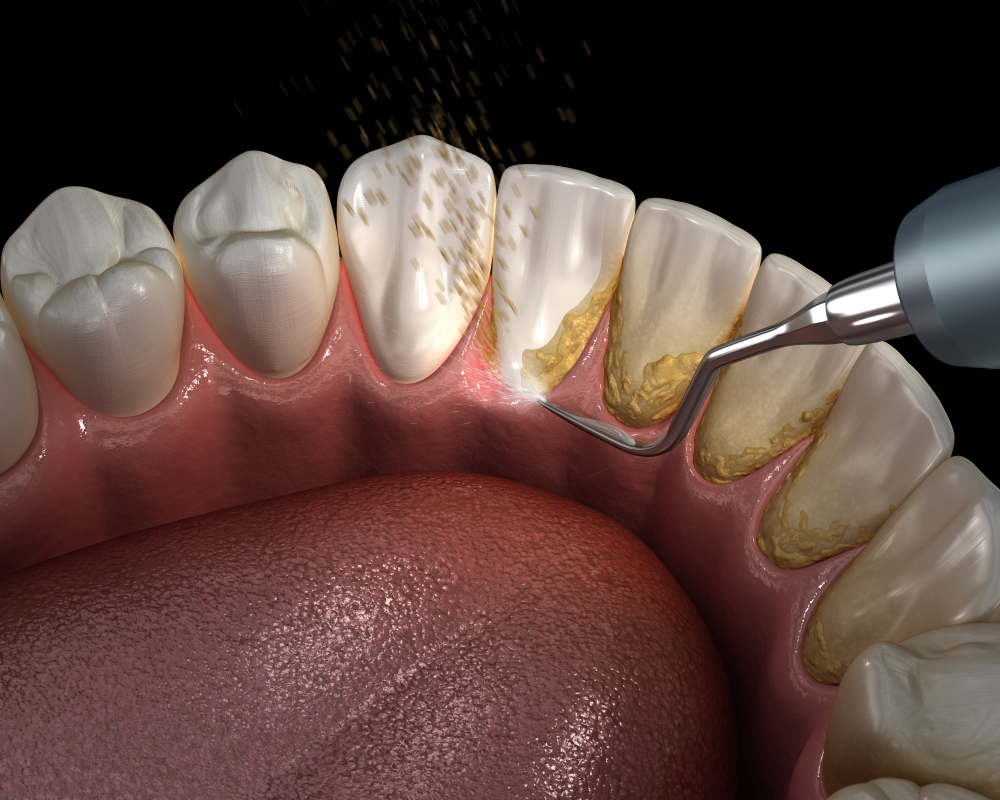

Diş taşı temizliği, ağız ve diş sağlığının korunmasında temel bir adımdır. Günlük fırçalama ve diş ipi kullanımı, ağız hijyenine büyük katkı sağlasa da zamanla dişlerin üzerinde biriken plaklar sertleşerek diş taşına dönüşebilir. Bu sert tabaka, hem diş eti hastalıklarına zemin hazırlar hem de ağızda kötü kokuya neden olabilir.

Diş taşı temizliği işlemi, uzman diş hekimleri tarafından özel aletlerle gerçekleştirilir. Dişlerin yüzeyinde biriken tartar tabakası dikkatle temizlenir ve ardından diş yüzeyi parlatılarak bakterilere karşı daha dirençli hale getirilir. Bu işlem, genellikle ağrısızdır ve kısa sürede tamamlanır.

Diş taşı temizliği, yalnızca sağlık açısından değil estetik açıdan da önemlidir. Özellikle diş beyazlatma işlemi öncesinde yapılması, çok daha etkili ve homojen sonuçlar alınmasını sağlar. Beyazlatma ajanlarının diş yüzeyine eşit dağılabilmesi için temiz bir yüzey şarttır.

Gülüş tasarımı yaptırmayı düşünenler için de diş taşı temizliği ilk adımdır. Sağlıklı diş etleri, başarılı bir estetik gülüş tasarımı için olmazsa olmazdır. Aynı zamanda estetik dolgu gibi uygulamalardan önce de bu temizlik işlemi önerilir.

Diş taşı temizliği, ihmal edilmemesi gereken bir bakım türüdür. Uzun süre temizlik yapılmadığında, diş etlerinde çekilme, kanama ve hatta diş çekimi gibi ileri işlemler gerekebilir. Bu yüzden yılda en az 1 kez diş taşı temizliği yaptırmak, hem estetik hem de sağlık açısından büyük fayda sağlar.